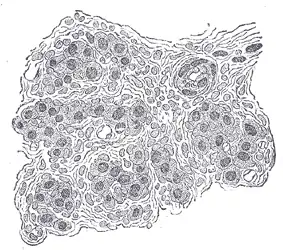

Section of part of human carotid body. Highly magnified. Numerous blood vessels are seen in section among the cells.

The carotid body is a small cluster of peripheral chemoreceptor cells and supporting sustentacular cells situated at the bifurcation of each common carotid artery in its tunica externa.[1][2]

The carotid body is made up of two types of cells, called glomus cells: glomus type I cells are peripheral chemoreceptors, and glomus type II cells are sustentacular supportive cells.